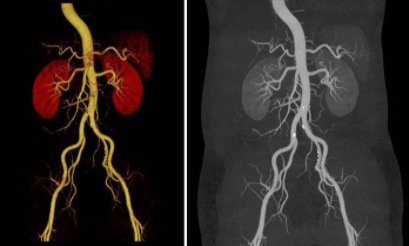

腹部CTA适用于肝、胰、脾、肾等实质性脏器的疾病诊断,尤其是在小病灶和早期肿瘤的发现及病变范围的显示上具有极大的优势。